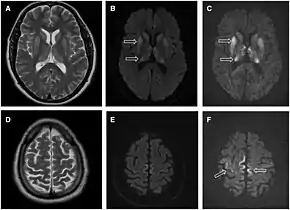

Magnetic resonance image of sporadic CJD[2]

Through the image of MRI, the obvious precipitation of prion protein in the brain is visible.

• MRI of the brain – often shows high signal intensity in the caudate nucleus and putamen bilaterally on T2-weighted images.

Imaging

Imaging of the brain may be performed during medical evaluation, both to rule out other causes and to obtain supportive evidence for diagnosis. Imaging findings are variable in their appearance, and also variable in sensitivity and specificity.[43] While imaging plays a lesser role in diagnosis of CJD,[44] characteristic findings on brain MRI in some cases may precede onset of clinical manifestations.[45]

Brain MRI is the most useful imaging modality for changes related to CJD. Of the MRI sequences, diffuse-weighted imaging sequences are most sensitive.[46] Characteristic findings are as follows:

dwMRI, FDG PET and post mortem histology from a patient who presented with sCJD aged 66

• Focal or diffuse diffusion-restriction involving the cerebral cortex and/or basal ganglia. In about 24% of cases DWI shows only cortical hyperintensity; in 68%, cortical and subcortical abnormalities; and in 5%, only subcortical anomalies.[47] The most iconic and striking cortical abnormality has been called "cortical ribboning" or "cortical ribbon sign" due to hyperintensities resembling ribbons appearing in the cortex on MRI.[48] The involvement of the thalamus can be found in sCJD, is even stronger and constant in vCJD.[49]

• Varying degree of symmetric T2 hyperintense signal changes in the basal ganglia (i.e., caudate and putamen), and to a lesser extent globus pallidus and occipital cortex.[44]

• Cerebellar atrophy